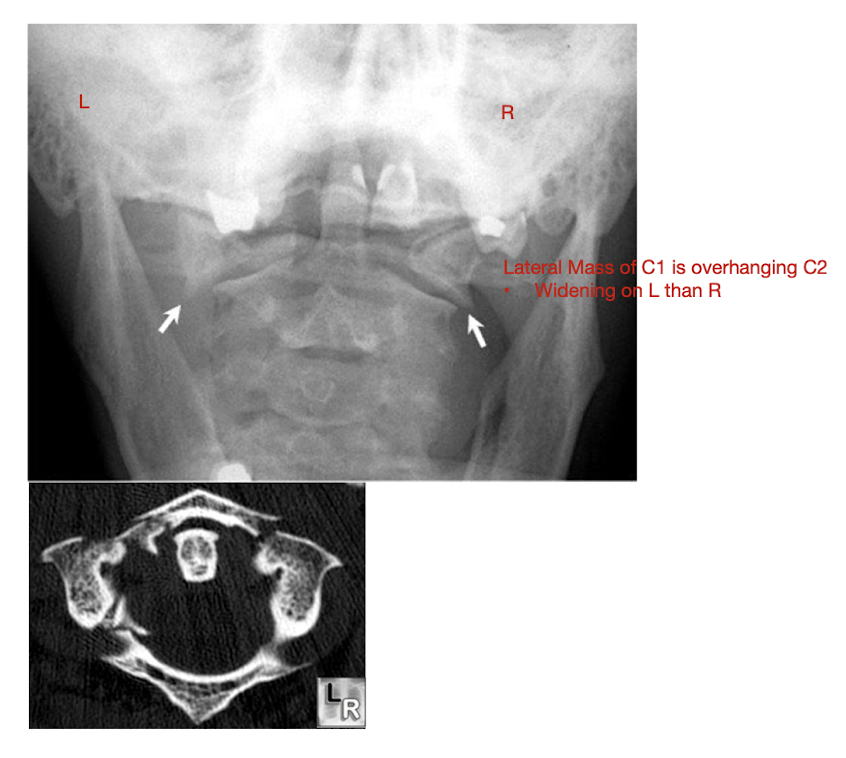

Fracture of C1: Jefferson Fx

Fracture of C1: Jefferson Fx

Rarely causes ___ injury

What direction of neck movement can cause head to slide forwards and compress SC?

Requires what type of view to diagnose?

Note displacement of what structure?

Neurological Injury

Fwd flex w Jefferson Fx

Open mouth view

Lateral Mass Displacement